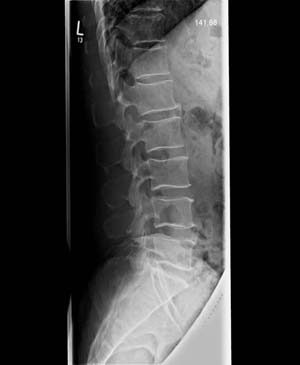

Röntgendiagnostik

Das konventionelle Röntgen stellt nach wie vor ein wichtiges Verfahren in der Diagnostik orthopädischer Krankheitsbilder und Verletzungen dar und kann durch neuere bildgebende Methoden wie Kernspintomographie (MRT) oder Computertomographie (CT) ergänzt, aber nicht ersetzt werden.

Unsere Praxis verfügt über ein hochmodernes volldigitales Röntgensystem, das sich durch eine extrem geringe Strahlenbelastung auszeichnet.

Durch die integrierte Steuerung von Röntgengenerator und hochauflösender Detektoreinheit entstehen innerhalb von Sekunden Röntgenaufnahmen in exzellenter Qualität, die durch computergestützte Applikationen befundet, archiviert sowie bei Bedarf auf CD oder DVD gespeichert werden können.